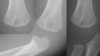

X-ray : 상완골 원위 골단판 골절(Transphyseal distal humerus fracture)

1. AP view에서 상완골에 대해 요척골은 전위되어 있으나 요골과 척골의 상호관계는 정상

2. 주관절 탈구, 외과 골절, 상완골 과상부 골절과의 감별진단이 중요